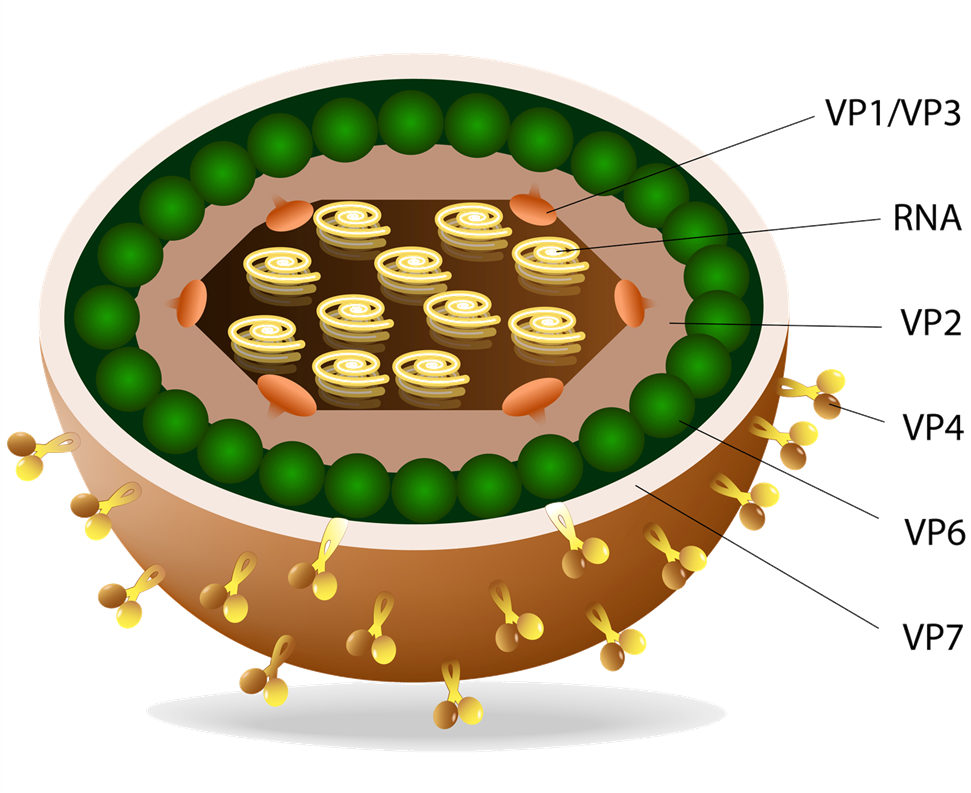

SIBO

Elevated numbers of small intestinal bacterial populations are to blame for GERD

Katherine’s results revealed a very intense SIBO produced gas signal along with a deeply disordered microflora. Besides commensal microbes whose levels were diminished, two Citrobacter species were detected in pathogenic amounts. Two many protein fragments were recovered on stool whereas several vitamin and nutrient deficiencies could be attributed to malabsorption. Finally, zonulin was recovered in very high levels indicating augmented intestinal permeability. Hashimoto’s and leaky gut are part of a vicious cycle. Thyroiditis delays MMC, leading to SIBO which in turn increases intestinal permeability and permits food antigens to get into circulation.